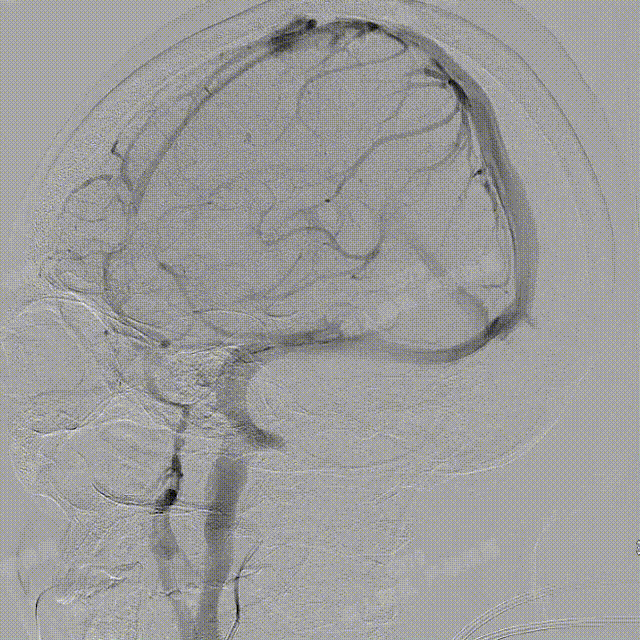

术中DSA造影:右侧颈内动脉侧位及3D造影,显示右侧颈内动脉后交通段动脉瘤。

术中DSA造影:左侧颈总动脉3D造影及左侧锁骨下正位造影。